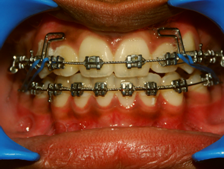

Tooth position can be corrected by Orthodontics, a branch of dentistry in which the teeth are moved into ideal and aesthetic positions using wires, elastics and brackets. The treatment is best done by a specialist who has completed a three years post graduate course in Orthodontics called an orthodontist.

Patient Undergoing Orthodontic Treatment

When light pressure is applied to a tooth using elastics, flexible wires and springs they move within the bone this is made possible since the teeth have a structure called the periodontal ligament which connects them to the bone. When pressure that is applied to the tooth is transmitted to the bone via the ligament the bone will resorb and the teeth will move in the desired direction.